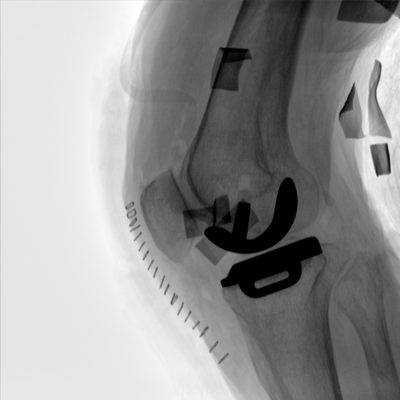

臨床適用科室:骨科、普通外科、矯形外科、創(chuàng)傷外科、泌尿外科、脊柱外科、疼痛外科、消化科、婦科等科室。

大尺寸動態(tài)平板探測器,高DQE、低噪聲、圖像清晰。采用多分辨率圖像增強(qiáng)處理技術(shù),不同部位不同圖像處理算法,滿足客戶多樣化的需求。